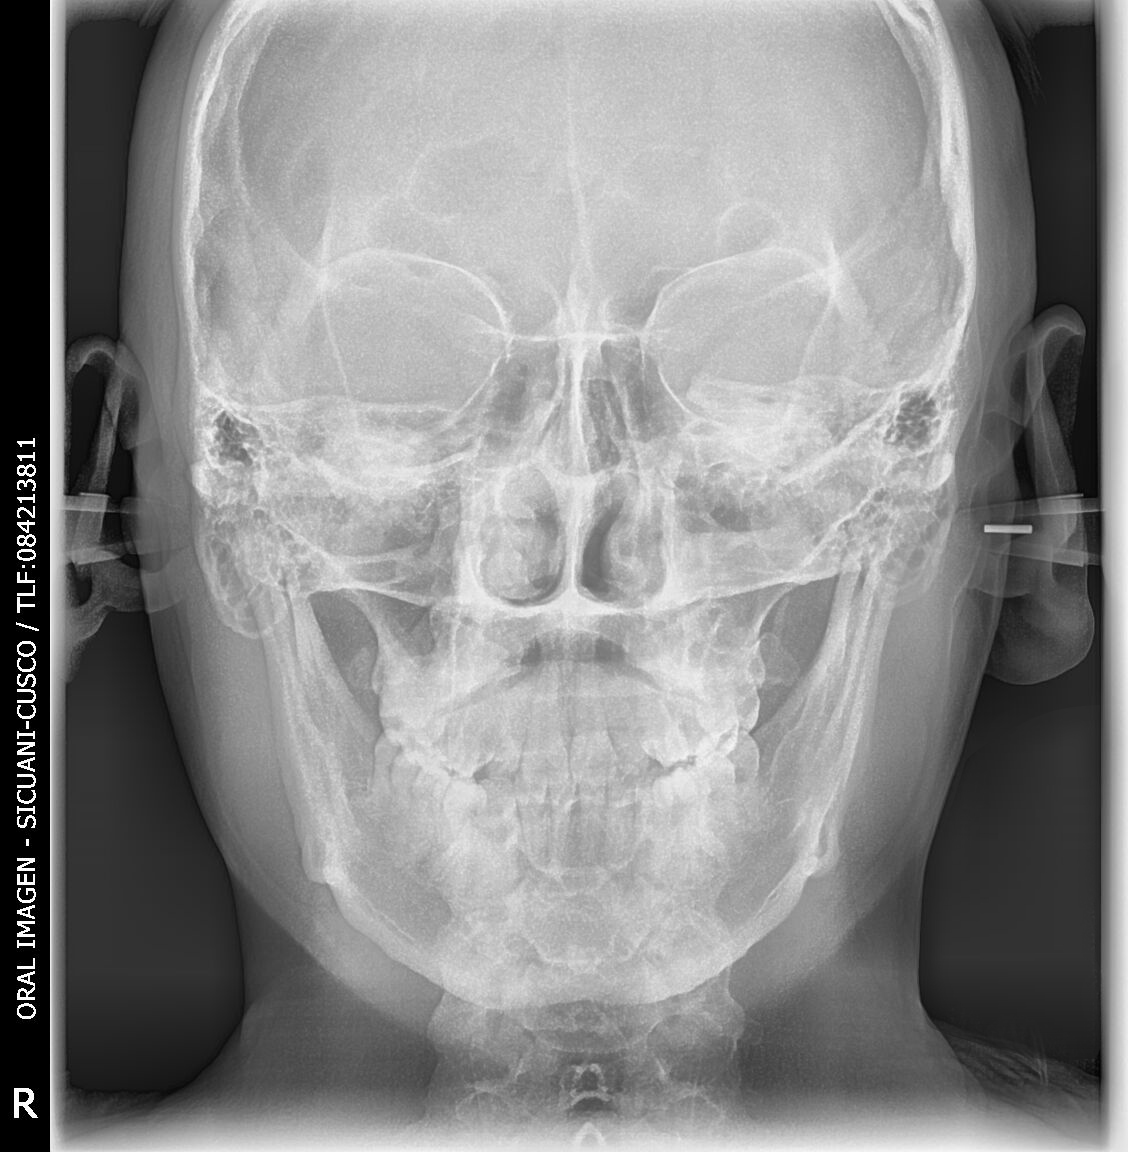

Gracias al Dr. JOSE TAYA MIRANDA, por confiar en nosotros y haber adquirido el paquete completo. Centro de diagnosticos, ubicado en la Av. Manuel Callo 457 - Sicuani-Cusco, instalación de equipo PaX-iSC (Panorámico-Cefalometrico),EzSensor Classic y EzRay Air de la marca VATECH.